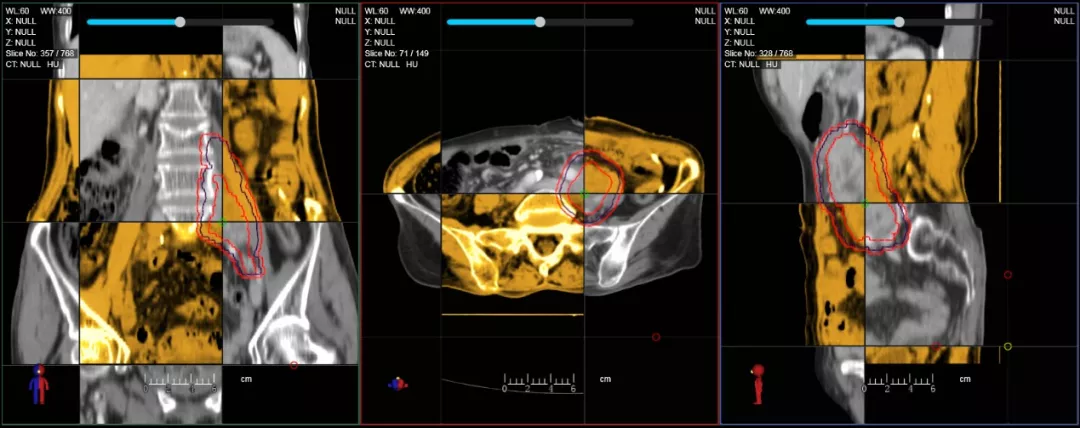

個體化自適應(yīng)放療

一體化CT-linac讓自適應(yīng)放療ART概念變?yōu)楝F(xiàn)實?;颊呷煶虪顟B(tài)監(jiān)控,適時在線調(diào)整治療計劃,精準(zhǔn)控制治療劑量,為患者動態(tài)定制個體化治療方案。uAI賦能智能勾畫和自動計劃,秒級勾勒靶區(qū)和危及器官,大幅縮短自適應(yīng)放療時間。

在線自適應(yīng)放療流程示意圖